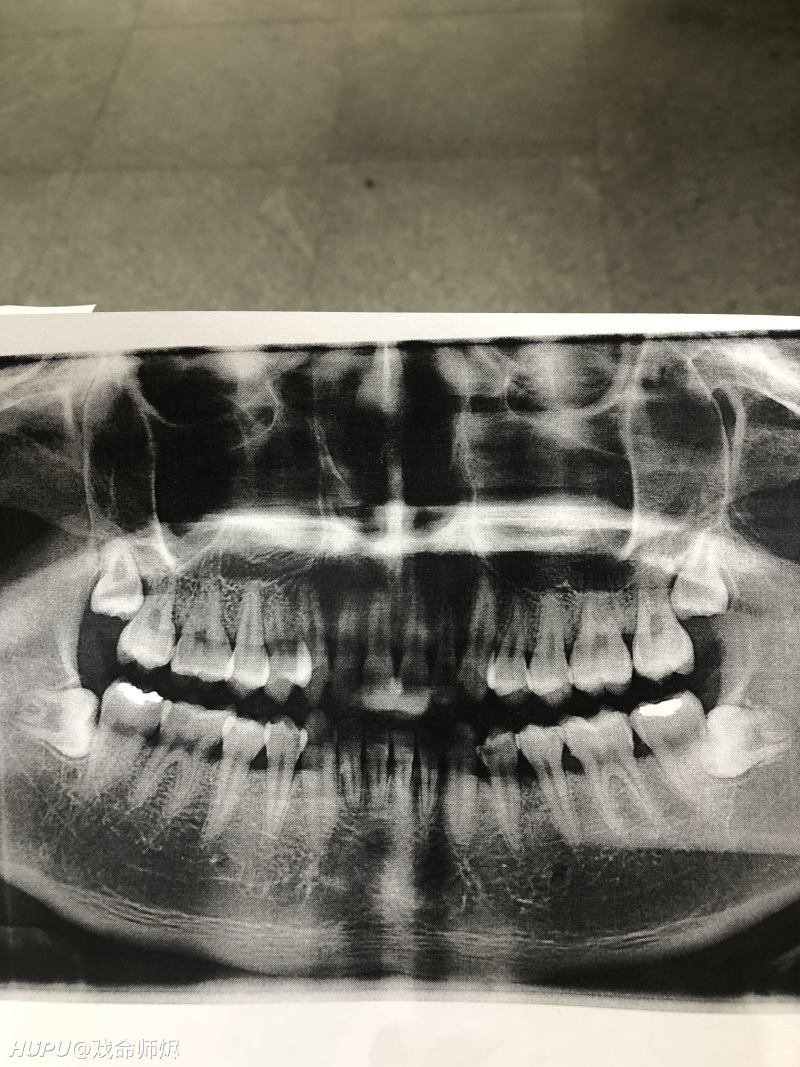

正常健康的牙片图片,正常牙片图

(图为28岁男性全口牙片,已补了三颗六龄牙,其中一颗连牙髓都坏死了)